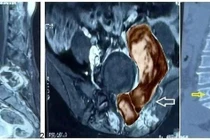

Bệnh nhân N.V.T. (48 tuổi, tỉnh Vĩnh Long) nhập viện với triệu chứng đau âm ỉ vùng hạ sườn trái, đầy tức nhẹ và mệt mỏi. Kết quả chẩn đoán hình ảnh xác định khối u dạng nang kích thước 6x6cm, chiếm gần hai phần ba thể tích lách. Sau khi hội chẩn liên khoa, các bác sĩ thống nhất chỉ định phẫu thuật cắt lách bằng phương pháp nội soi.

Theo các bác sĩ, u lách dạng nang là bệnh lý rất hiếm, chỉ chiếm dưới 1% trong các tổn thương của lách. Phần lớn trường hợp được phát hiện tình cờ khi siêu âm hoặc chụp CT. Khi khối u lớn, người bệnh có nguy cơ chèn ép, vỡ hoặc nhiễm trùng, do đó phẫu thuật cắt lách là giải pháp điều trị tối ưu.